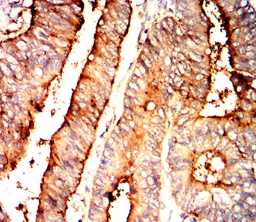

CEACAM6 Mouse Monoclonal antibody[4B9F1]

This gene encodes a protein that belongs to the carcinoembryonic antigen (CEA) family whose members are glycosyl phosphatidyl inositol (GPI) anchored cell surface glycoproteins. Members of this family play a role in cell adhesion and are widely used as tumor markers in serum immunoassay determinations of carcinoma. This gene affects the sensitivity of tumor cells to adenovirus infection. The protein encoded by this gene acts as a receptor for adherent-invasive E. coli adhesion to the surface of ileal epithelial cells in patients with Crohn's disease. This gene is clustered with genes and pseudogenes of the cell adhesion molecules subgroup of the CEA family on chromosome 19.

IHC    1/200 - 1/1000